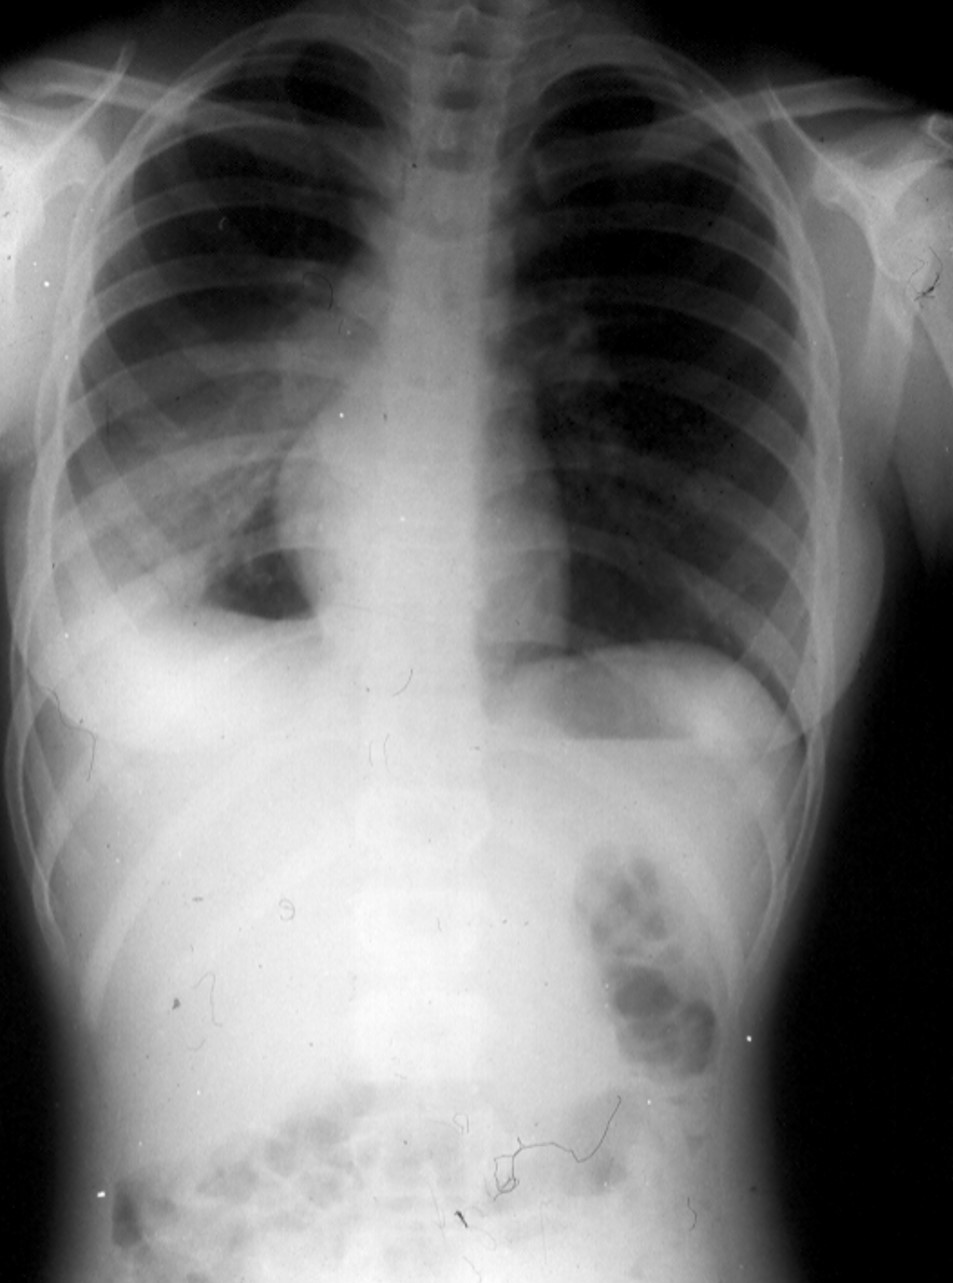

You are shown a x-ray of the chest and abdomen and a photograph of the oropharynx

(see panels A and B below) of a 19-year-old women whose chief complaints include,

fever, malaise, and sore throat of 7-days duration. You are given no other information.

Panel A. The chest x-ray shows a segmental right lower lobe pneumonia, right-sided

mediastinal and paratracheal adenopathy, and mediastinal rotation and shift to the

right.

Pneumonia, usually segmental and associated with mediastinal adenopathy, occurs in

about 5% of EBV-MN patients.

The abdominal portion of the film shows splenomegaly (note the shift of the

gastric bubble to the right). It is important to remember that enlarged spleens can

rupture with overvigorous palpation; this is particularly true in patients with EBV-MN.